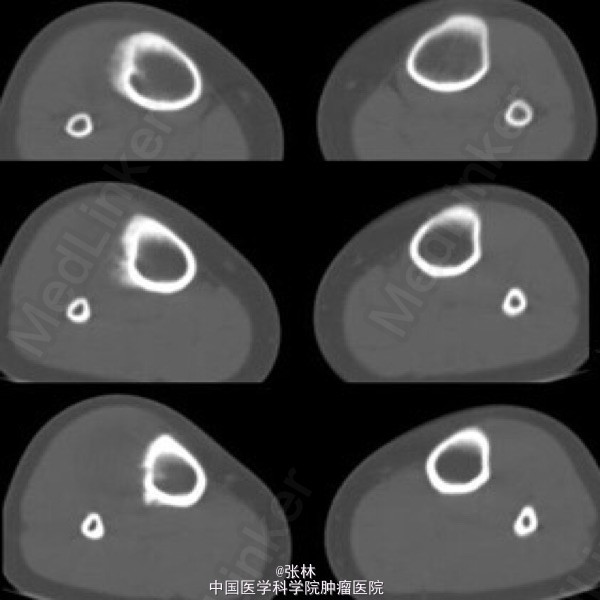

【病史临床】患者,女性,11岁,右侧胫骨上段触痛,血象及皮温不高。

影像表现:右胫骨外侧骨皮质表面低密度软组织肿块,与骨干长轴平行,基底部有条状钙化影,肿块边缘有骨膜新生骨,骨皮质内面未受侵犯,肿块与骨皮质间无透亮间隙。

术后病理结果:尤文氏肉瘤(IIb期)